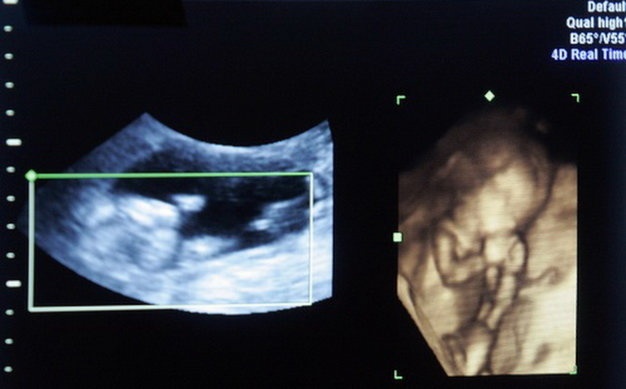

| Rất nhiều những ông bố bà mẹ khao khát từng ngày để có một đứa con - Ảnh minh hoạ. |

“5 năm là vợ chồng, đã có 7 lần tôi mang thai, nhưng cứ đến tháng thứ 4, thứ 5 thì thai lại bị lưu vì trước đó hậu quả của việc nạo phá thai không an toàn khiến cho tôi bị mỏng thành tử cung. Vợ chồng tôi “khát” một đứa con mà đợi mòn mỏi cũng không được”, chị buồn bã.